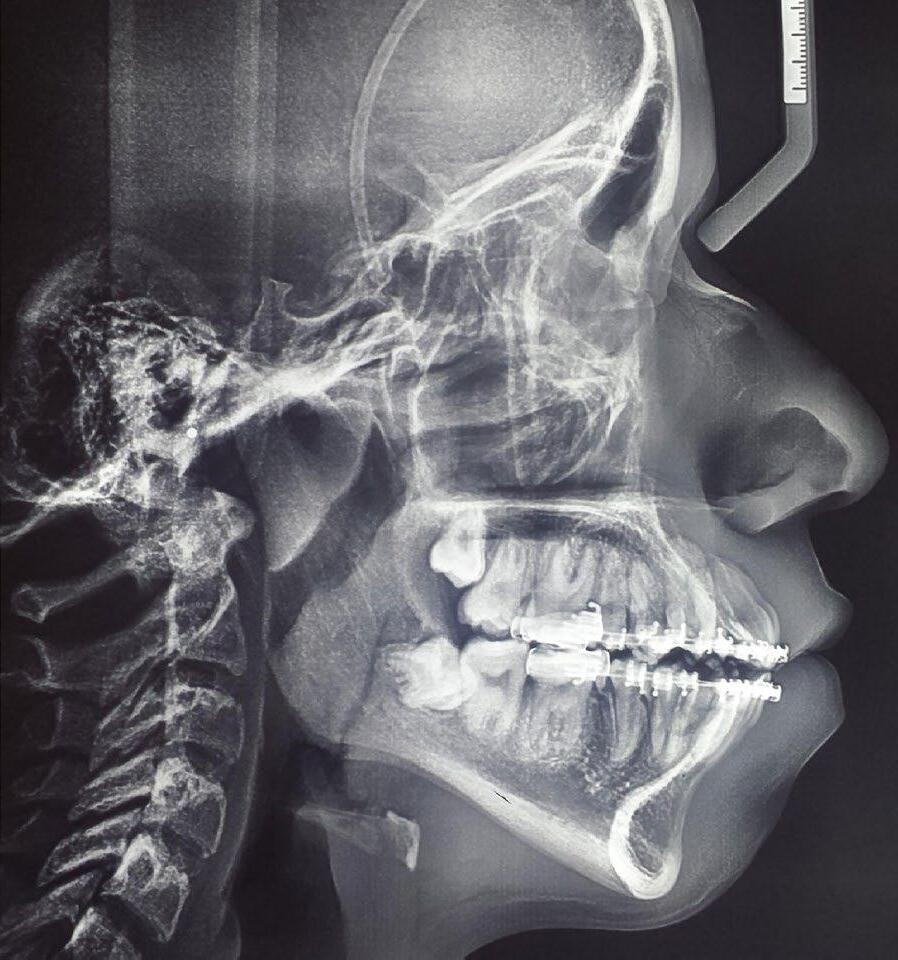

Se presenta un paciente de 18 años de edad que refiere tener hemofilia tipo A, moderado grado V. En los estudios de inicio extraorales, se observa en la Figura 1 el frente, sonrisa y perfil. En la radiografía lateral de inicio (Figura 2) se evidencian el overjet y overbite reducidos, clase I esquelética, hiperdivergencia y biprotrusión dentoalveolar.

Figura 2. Rx lateral de cráneo inicio.

El tratamiento concluyó en 2 años y 6 meses, logrando el perfil facial deseado, con clase I esquelética, clase I canina y molar bilaterales, corrección del apiñamiento maxilar y mandibular, líneas medias coincidentes, overjet y overbite adecuados, así como la realización de la genioplastia e implantes en la zona malar. En los

estudios radiográficos finales, en la lateral de cráneo, se observa la diferencia tras 2 años de iniciado el tratamiento (Figura 8), además de la radiografía panorámica final. Debido a la forma del perfil, y con el fin de alcanzar la estética deseada, se realizó la cirugía.